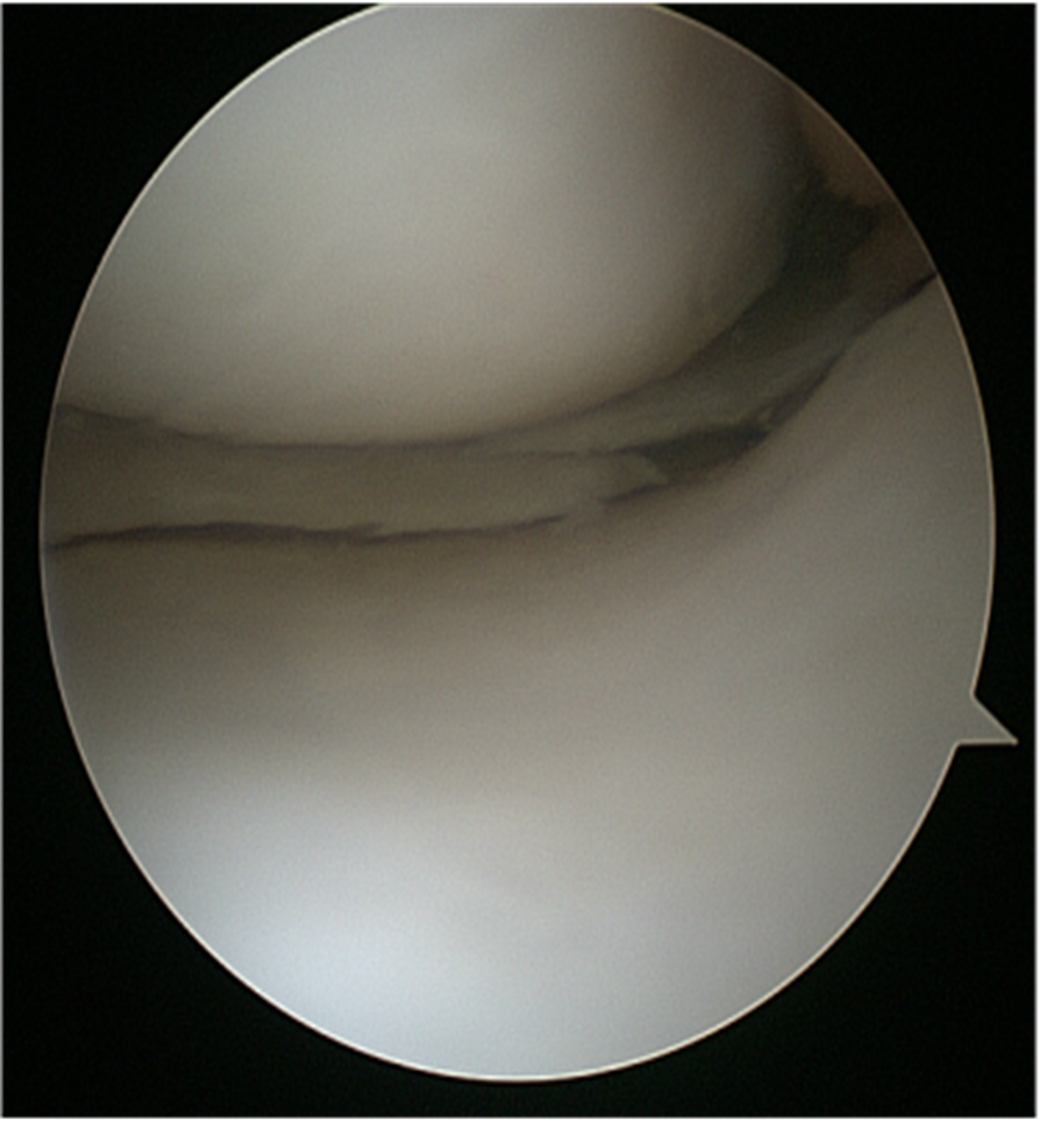

A torn meniscus is one of the most common knee injuries. The cartilage between your shinbone and thighbone is shaped like a C and acts as a cushion. A torn meniscus causes pain, swelling and stiffness. You also might feel a block to knee motion and have trouble extending your knee fully.

How is Torn Meniscus Diagnosed?

X-rays. Because a torn meniscus is made of cartilage, it won’t show up on X-rays. But X-rays can help rule out other problems with the knee that cause similar symptoms.

MRI. This uses a strong magnetic field to produce detailed images of both hard and soft tissues within your knee. It’s the best imaging study to detect a torn meniscus.

How is Torn Meniscus treated?

If your knee isn’t responding to the treatments above, your doctor may recommend arthroscopic surgery. Your doctor will give you specific instructions as to how to prepare for this surgery.